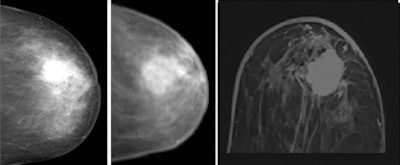

Medical image registration software can match different modalities, as in the case of PET/CT. The authors think that no report of breast registration at 3 tesla has been published to date, and this prompted them to conduct a pilot study. MR-M was acquired on a high-field clinical scanner at 3 tesla (Magnetom Trio, Siemens Healthcare), while x-ray mammography was performed on a full-field digital system (Selenia, Hologic). They enrolled seven patients with clearly delineable lesions with a diameter greater than 10 mm (Eur J Radiol, 13 May 2011).

The team matched x-ray mammography and MR-M using a dedicated image registration algorithm that allows semiautomatic nonlinear deformation of MR-M, based on finite-element modeling. To identify registration errors, a virtual craniocaudal 2D mammogram was calculated by the in-house software from MR-M (with and without gadodiamide [Gd]) and matched with corresponding x-ray mammograms. To quantify registration errors, the geometric center of the lesions in the virtual versus conventional mammogram was subtracted. The robustness of registration was quantified by registration of x-ray mammograms to both MR mammograms with and without gadodiamide.

Image registration was performed successfully for all patients. The overall registration error was 8.2 mm (1 minute after Gd; confidence intervaI [CI]: 2.0-14.4 mm, standard deviation [SD]: 6.7 mm) versus 8.9 mm (no Gd; CI: 4.0-13.9 mm, SD: 5.4 mm). The mean difference between pre- versus postcontrast was 0.7 mm (SD: 1.9 mm).